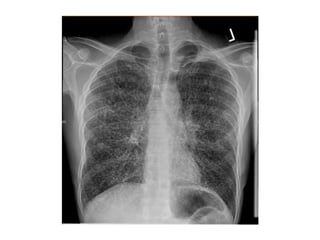

Blastomicosis: Rx de tórax

• Infiltrados focales alveolares en

lóbulos superiores, a menudo de

aspecto nodular

• Cavitaciones frecuentes (1/3 de los

casos)

• El 15 % masa que se confunde con Ca

• Patron micronodular < del 1%.

• Adenopatías y calcificaciones raras.

Blastomicosis: Rx detórax • Infiltrados focales alveolares en lóbulos superiores, a menudo de aspecto nodular • Cavitaciones frecuentes (1/3 de los casos) • El 15 % masa que se confunde con Ca • Patron micronodular < del 1%. • Adenopatías y calcificaciones raras.